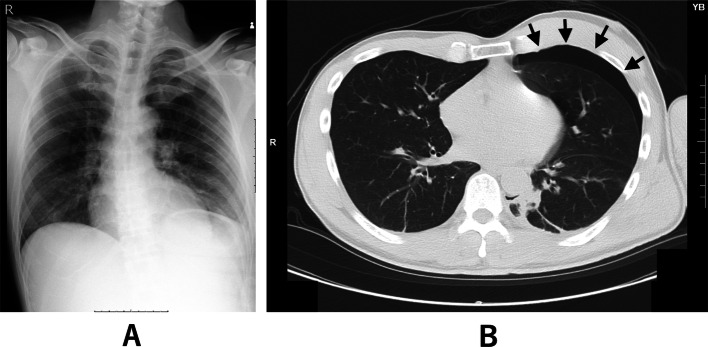

Postoperatively, chest radiography performed while OLV was still in place showed decreased inflation of the left lung (Fig. 3A). Gentle manual ventilation was performed for approximately 1 min at airway pressures of 10–15 cmH₂O, and a follow-up chest radiograph confirmed re-expansion of the left lung (Fig. 3B). The patient was then awakened and extubated. On postoperative day 1, chest radiography showed further improvement in left lung inflation and no evidence of pneumothorax (Fig. 4). The patient had no postoperative complications and was discharged home on postoperative day 2. The patient remained well during outpatient follow-up, with no evidence of pneumothorax recurrence or respiratory symptoms.

Fig. 3.

A Chest radiography while OLV was still in place showed decreased inflation of the left lung. B Left lung inflation improved after about one minute of gentle manual ventilation